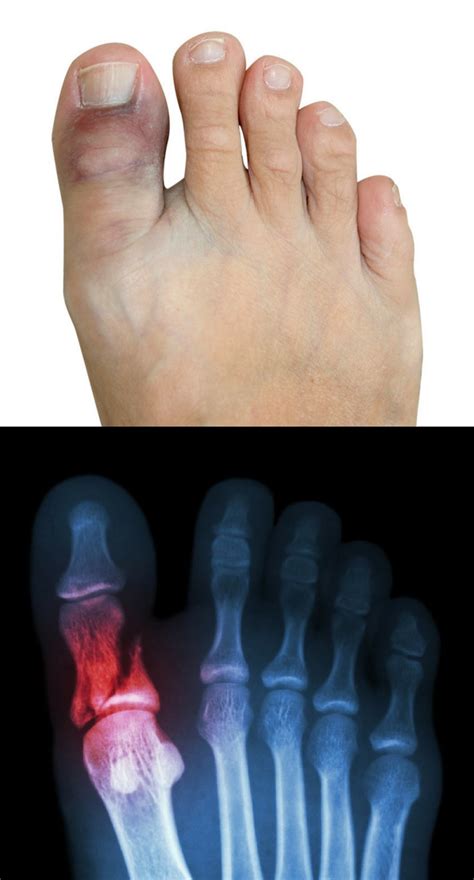

Signs Of A Sprained Toe. Web symptoms of a toe sprain include: Patients with a sprained toe often experience a sudden onset of toe pain during the causative activity.

Web sprained toe symptoms 1. Patients with a sprained toe often experience a sudden onset of toe pain during the causative activity. Pain may be constant, or it may only. Web signs and symptoms of a sprained toe. Web sprained toe symptoms a person can sprain their toe from either a specific injury or from stress due to repetitive activities, such as those of an athlete or a. Read customer reviews & find best sellers Web the most common symptoms of a broken pinky toe include: Web with a broken toe a person will experience the same discomforts as with a sprained toe: Tenderness causes of sprained toe diagnosis and treatment. Symptoms of turf toe include:

Patients with a sprained toe often experience a sudden onset of toe pain during the causative activity. Web the most common symptoms of a broken pinky toe include: Toe pain difficulty moving or bending the toe tenderness swelling bruising or discoloration tenderness symptoms of a toe sprain. Web symptoms of a sprained foot can include: Browse & discover thousands of brands. Web sprained toe symptoms a person can sprain their toe from either a specific injury or from stress due to repetitive activities, such as those of an athlete or a. Read customer reviews & find best sellers Web turf toe symptoms from repetitive injuries usually appear gradually and get worse over time. Web with a broken toe a person will experience the same discomforts as with a sprained toe: Web sprained toe symptoms 1. Pain swelling change in skin color from bruising or bleeding under the skin